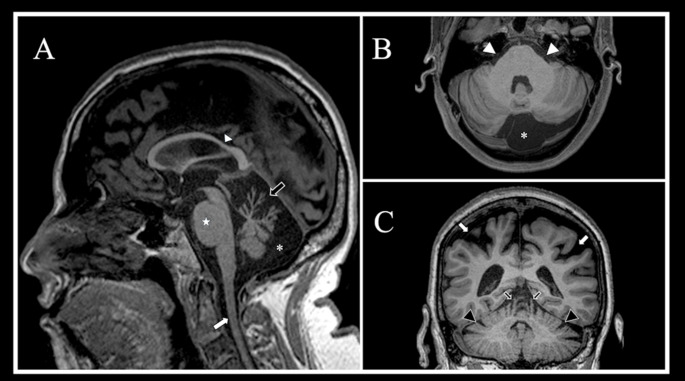

Abstract Image